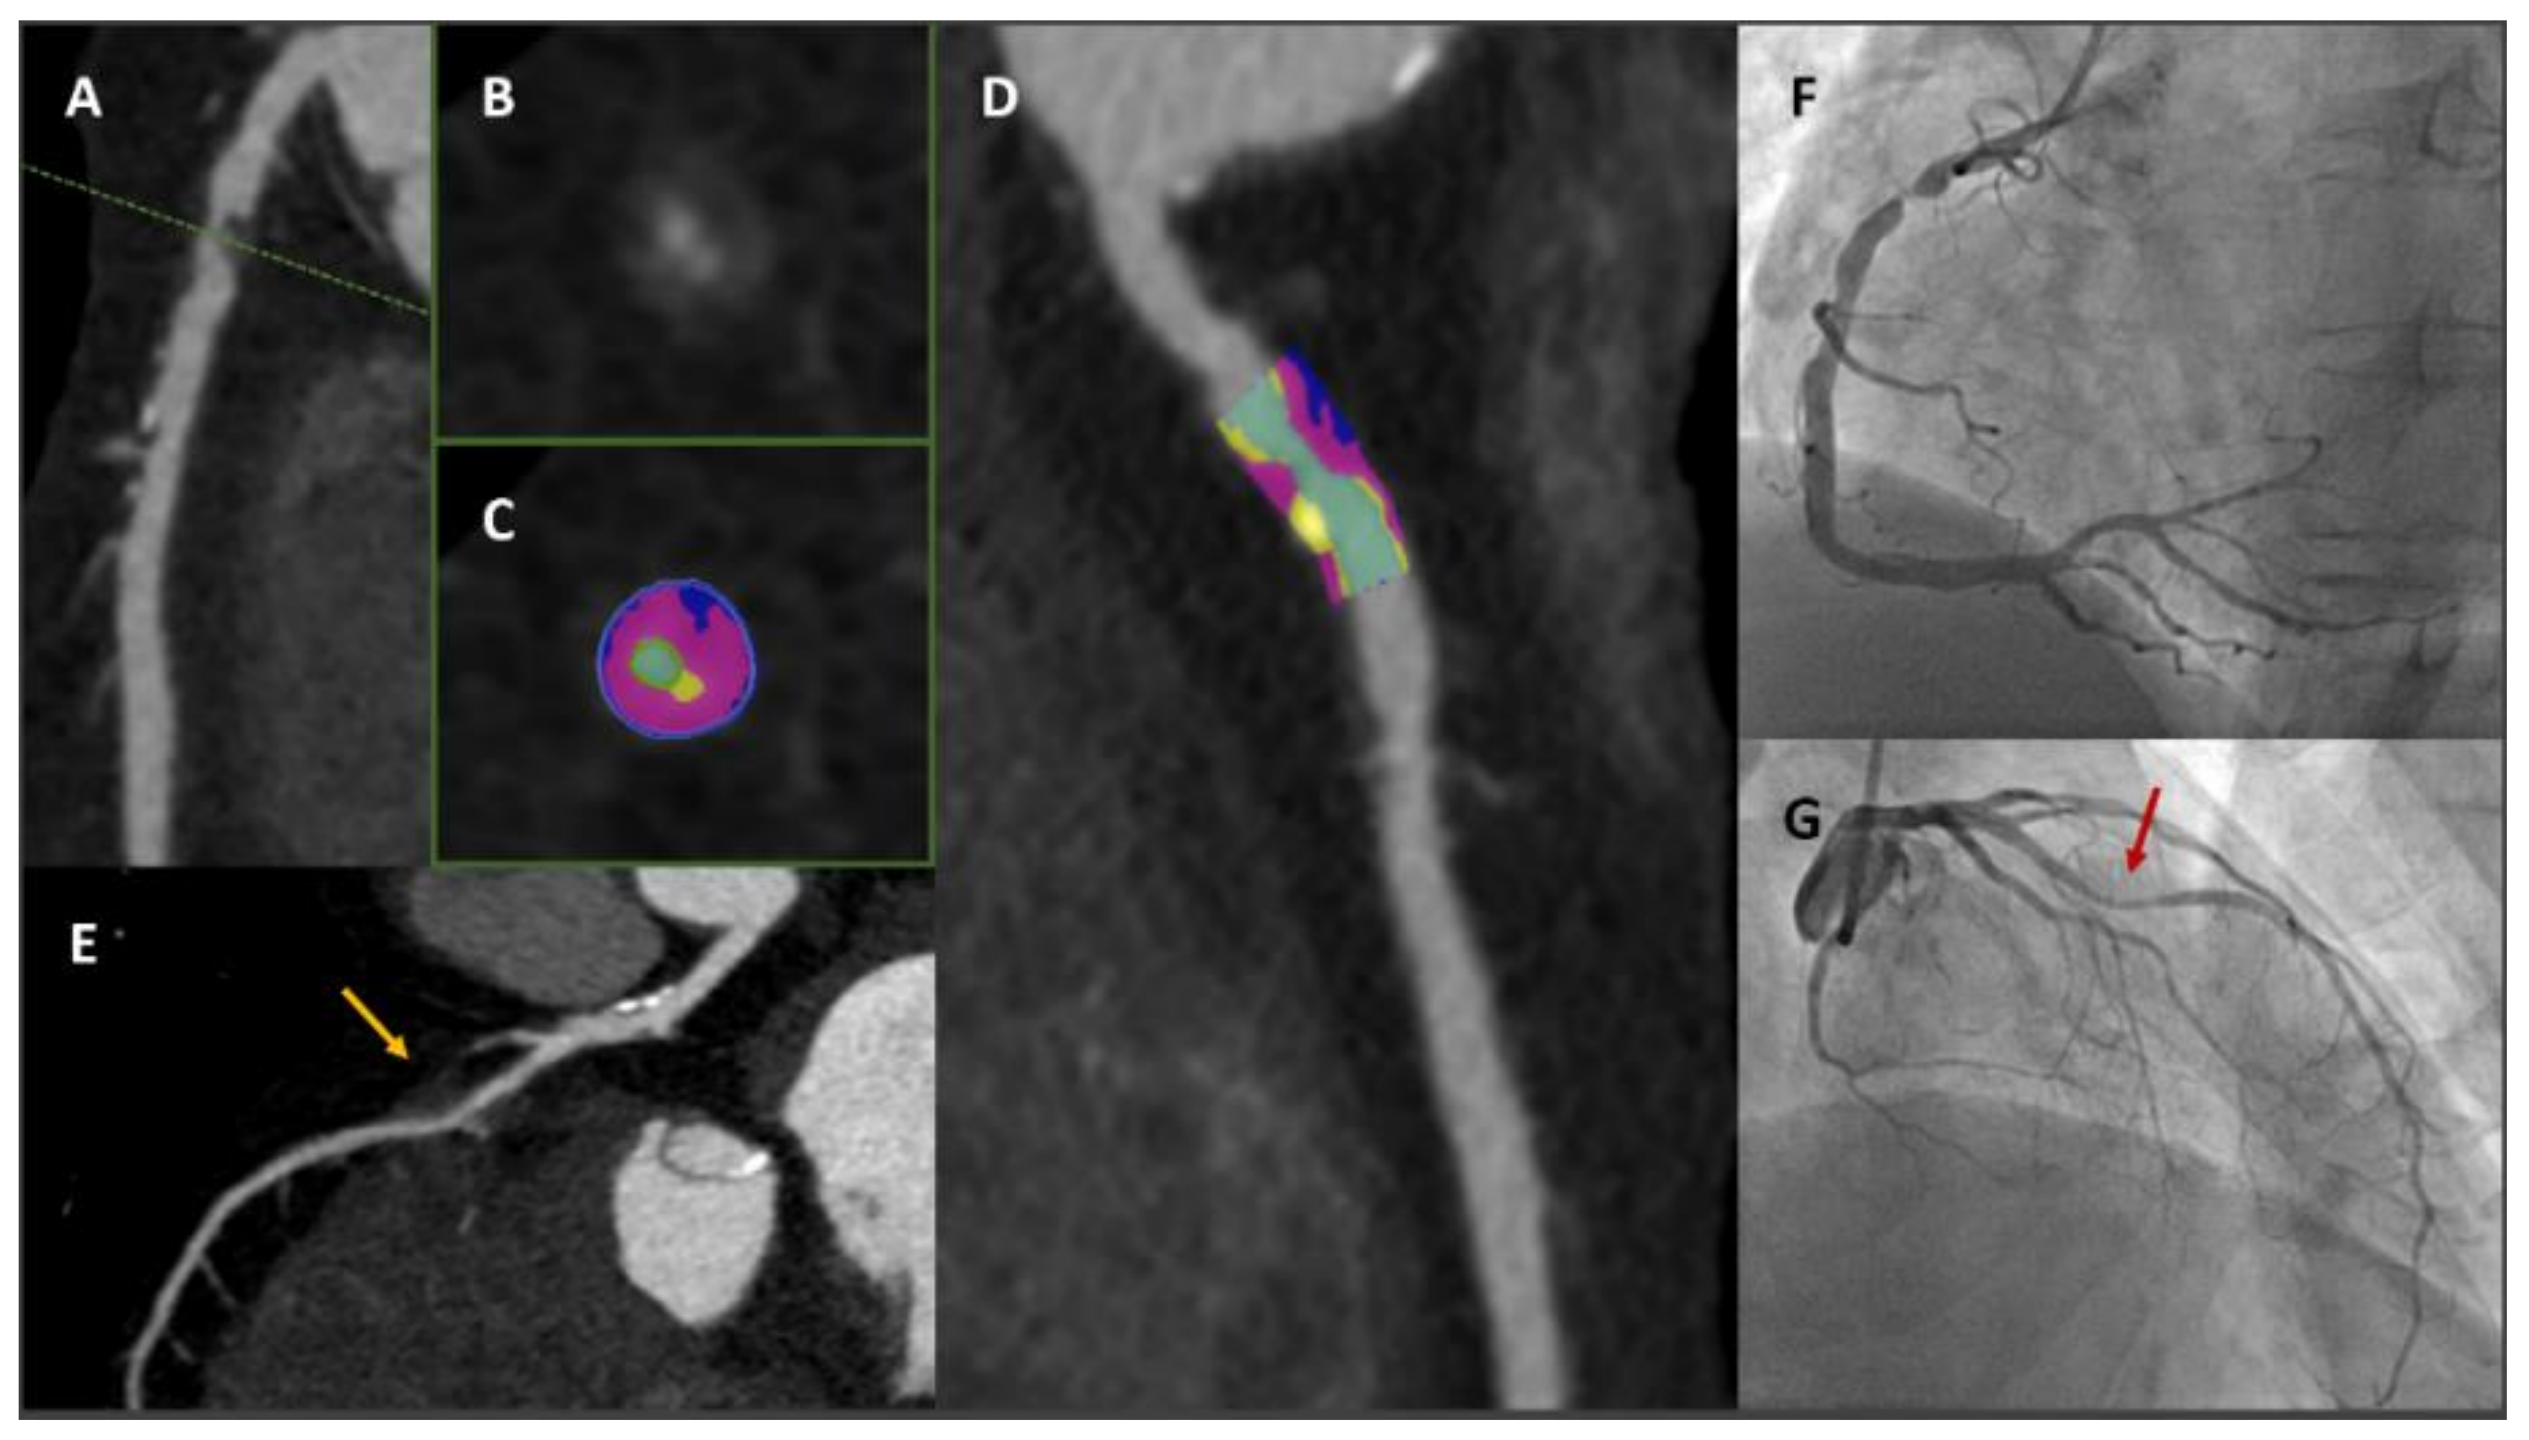

- Greenland, P.; Blaha, M.J.; Budoff, M.J.; Erbel, R.; Watson, K.E. Coronary Calcium Score and Cardiovascular Risk. J. Am. Coll. Cardiol. 2018, 72, 434–447. [Google Scholar] [CrossRef]

- Maurovich-Horvat, P.; Hoffmann, U.; Vorpahl, M.; Nakano, M.; Virmani, R.; Alkadhi, H. The napkin-ring sign: CT signature of high-risk coronary plaques? JACC Cardiovasc. Imaging 2010, 3, 440–444. [Google Scholar] [CrossRef] [Green Version]

- Motoyama, S.; Sarai, M.; Harigaya, H.; Anno, H.; Inoue, K.; Hara, T.; Naruse, H.; Ishii, J.; Hishida, H.; Wong, N.D.; et al. Computed tomographic angiography characteristics of atherosclerotic plaques subsequently resulting in acute coronary syndrome. J. Am. Coll. Cardiol. 2009, 54, 49–57. [Google Scholar] [CrossRef] [PubMed] [Green Version]

- Narula, J.; Nakano, M.; Virmani, R.; Kolodgie, F.D.; Petersen, R.; Newcomb, R.; Malik, S.; Fuster, V.; Finn, A.V. Histopathologic characteristics of atherosclerotic coronary disease and implications of the findings for the invasive and noninvasive detection of vulnerable plaques. J. Am. Coll. Cardiol. 2013, 61, 1041–1051. [Google Scholar] [CrossRef] [Green Version]

- Hoffmann, U.; Moselewski, F.; Nieman, K.; Jang, I.K.; Ferencik, M.; Rahman, A.M.; Cury, R.C.; Abbara, S.; Joneidi-Jafari, H.; Achenbach, S.; et al. Noninvasive assessment of plaque morphology and composition in culprit and stable lesions in acute coronary syndrome and stable lesions in stable angina by multidetector computed tomography. J. Am. Coll Cardiol. 2006, 47, 1655–1662. [Google Scholar] [CrossRef] [Green Version]

- Chang, H.J.; Lin, F.Y.; Lee, S.E.; Andreini, D.; Bax, J.; Cademartiri, F.; Chinnaiyan, K.; Chow, B.J.W.; Conte, E.; Cury, R.C.; et al. Coronary Atherosclerotic Precursors of Acute Coronary Syndromes. J. Am. Coll Cardiol. 2018, 71, 2511–2522. [Google Scholar] [CrossRef] [PubMed]

- Ferencik, M.; Mayrhofer, T.; Bittner, D.O.; Emami, H.; Puchner, S.B.; Lu, M.T.; Meyersohn, N.M.; Ivanov, A.V.; Adami, E.C.; Patel, M.R.; et al. Use of High-Risk Coronary Atherosclerotic Plaque Detection for Risk Stratification of Patients With Stable Chest Pain: A Secondary Analysis of the PROMISE Randomized Clinical Trial. JAMA Cardiol. 2018, 3, 144–152. [Google Scholar] [CrossRef] [Green Version]

- Hoffmann, U.; Ferencik, M.; Udelson, J.E.; Picard, M.H.; Truong, Q.A.; Patel, M.R.; Huang, M.; Pencina, M.; Mark, D.B.; Heitner, J.F.; et al. Prognostic Value of Noninvasive Cardiovascular Testing in Patients With Stable Chest Pain: Insights From the PROMISE Trial (Prospective Multicenter Imaging Study for Evaluation of Chest Pain). Circulation 2017, 135, 2320–2332. [Google Scholar] [CrossRef] [PubMed]

- Williams, M.C.; Moss, A.J.; Dweck, M.; Adamson, P.D.; Alam, S.; Hunter, A.; Shah, A.S.V.; Pawade, T.; Weir-McCall, J.R.; Roditi, G.; et al. Coronary Artery Plaque Characteristics Associated With Adverse Outcomes in the SCOT-HEART Study. J. Am. Coll. Cardiol. 2019, 73, 291–301. [Google Scholar] [CrossRef] [PubMed]

- Williams, M.C.; Kwiecinski, J.; Doris, M.; McElhinney, P.; D’Souza, M.S.; Cadet, S.; Adamson, P.D.; Moss, A.J.; Alam, S.; Hunter, A.; et al. Low-Attenuation Noncalcified Plaque on Coronary Computed Tomography Angiography Predicts Myocardial Infarction: Results From the Multicenter SCOT-HEART Trial (Scottish Computed Tomography of the HEART). Circulation 2020, 141, 1452–1462. [Google Scholar] [CrossRef] [PubMed] [Green Version]

- Lee, J.M.; Choi, G.; Koo, B.K.; Hwang, D.; Park, J.; Zhang, J.; Kim, K.J.; Tong, Y.; Kim, H.J.; Grady, L.; et al. Identification of High-Risk Plaques Destined to Cause Acute Coronary Syndrome Using Coronary Computed Tomographic Angiography and Computational Fluid Dynamics. JACC Cardiovasc. Imaging 2019, 12, 1032–1043. [Google Scholar] [CrossRef]